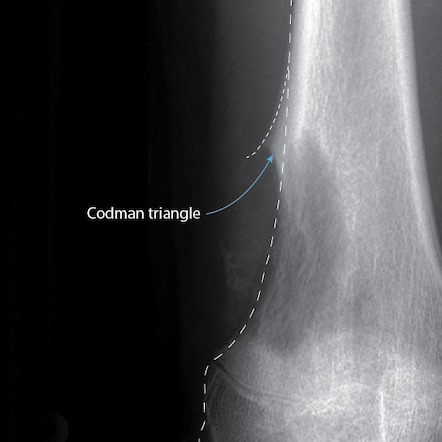

3.4) Triángulo de Codman

Definición y aspecto radiológico

Elevación del periostio en los bordes de una lesión que crece rápidamente, con formación de hueso reactivo solo en los extremos del periostio levantado. En la radiografía, se ve como una pequeña espícula triangular en la unión entre la lesión y la cortical normal.

El nombre es un término histórico; no es un triángulo completo, sino un ángulo formado por el periostio elevado y la cortical.

Significado

Crecimiento extremadamente rápido. Indica muy alta agresividad. Es un signo clásico de tumor maligno, pero no es patognomónico.

Causas

- Osteosarcoma.

- Sarcoma de Ewing.

- Osteomielitis aguda.

- Metástasis.